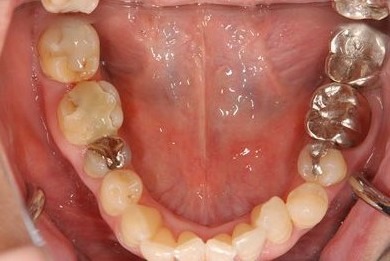

| 性別/年齢 | 女性 / 50歳 | ||||||||||||||||||||||||||||||||

| 主訴 | 銀のかぶせが取れたところと、痛みがある歯をセラミックで治療したい。 | ||||||||||||||||||||||||||||||||

| 治療内容 | メタルボンドセラミック3本(メタルボンドセラミッククラウン用土台3本) | ||||||||||||||||||||||||||||||||

| 総治療費 | 374,063円 | ||||||||||||||||||||||||||||||||

| 治療期間 | 10ヶ月 |